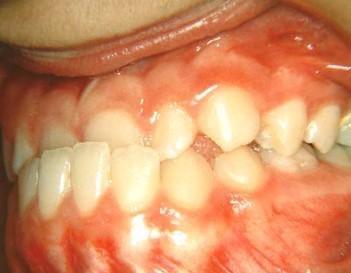

1η περίπτωση

Αρχική οδοντοσκελετική κατάσταση παιδιού με προγναθισμό άνω γνάθου και έντονη οριζόντια πρόταξη άνω τομέων Η σημασία της στοματικής υγιεινής και ορθοδοντικής

026

πρόληψης

027 Αμέσως μετά το τέλος της ορθοδοντικής θεραπείας. Οι αλλαγές στην οδοντική του σύγκλειση αλλά και στο πρόσωπο είναι εμφανείς 15 χρόνια μετά την αρχική περάτωση της θεραπείας, το αποτέλεσμα παραμένει σταθερό και ο ασθενής απέκτησε ένα υγιές και αρμονικό χαμόγελο και πρόσωπο. Η σημασία της στοματικής υγιεινής και ορθοδοντικής πρόληψης